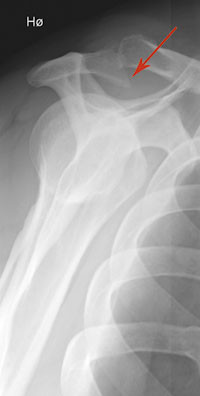

I de fleste tilfeller er ultralyd tilstrekkelig, målrettet MR rekvireres på utvidede indikasjoner ved atypiske funn og preoperativt. For pasienter med atraumatiske skulderlidelser vil klinisk undersøkelse eventuelt supplert med dynamisk bilateral ultralyd vanligvis gi tilstrekkelig grunnlag for konklusjon. For vurdering av rotatorcuffen inkludert rupturer samt bicepssenen er MR og ultralyd likeverdige (15), men pasientene er mer fornøyd med ultralyd (16). Ultralyd er beste metode for å vurdere kalknedslag. Figur 3 viser ultralyd og MR ved supraspinatusruptur. For revmatologen er ultralyd et nyttig hjelpemiddel for å skille mellom synovitt og tenosynovitt. Radiologiske forandringer ses hos de fleste pasienter med revmatoid artritt få år etter sykdomsdebut. Synovial inflammasjon kan medføre bruskforandringer og forringe skulderfunksjonen. Skjelettrøntgen med «outlet view» (fig 4) er først og fremst indisert ved traumatiske skulderlidelser, men kan gi opplysninger om større påleiringer på undersiden av akromion, grad av glenohumeral artrose og om sjeldne tilstander, slik som nekrose av caput humeri. Artrose i akromioklavikulærleddet ses hyppig hos pasienter eldre enn 50 år, men er vanligvis ikke smertefullt.